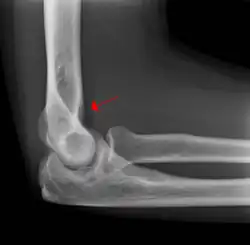

Fat pad sign

The fat pad sign, also known as the sail sign, is a potential finding on elbow radiography which suggests a fracture of one or more bones at the elbow. It may indicate an occult fracture that is not directly visible. Its name derives from the fact that it has the shape of a spinnaker (sail).[1] It is caused by displacement of the fat pad around the elbow joint. Both anterior and posterior fat pad signs exist, and both can be found on the same X-ray.

The fat pad sign is invaluable in assessing for the presence of an intra-articular fracture of the elbow. An anterior fat pad is often normal. However a posterior fat pad seen on a lateral x-ray of the elbow is always abnormal. The patient will be unable to flex their elbow and requires orthopaedic input.[2]

The posterior fat pad is normally pressed in the olecranon fossa by the triceps tendon, and hence invisible on lateral radiograph of the elbow.[3] When there is a fracture of the distal humerus, or other pathology involving the elbow joint, inflammation develops around the synovial membrane forcing the fat pad out of its normal physiologic resting place. This is visible as the "posterior fat pad sign" and is often the only visible marker of a fracture, particularly in the pediatrics population.